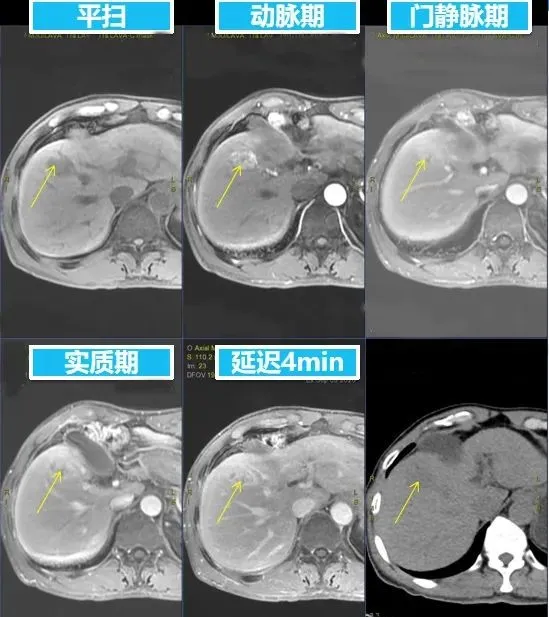

MR增强图像

▲PET-CT与融合增强MR对比图▲

PET-CT示:肝S5段可见一类圆形稍低密度影,边缘模糊,最大截面约1.75cm×2.79cm,PET示异常放射性摄取增高,SUV最高值4.43,平均值4.18,延迟扫描后,FDG摄取轻度减低,SUV最高值4.02,平均值3.95。